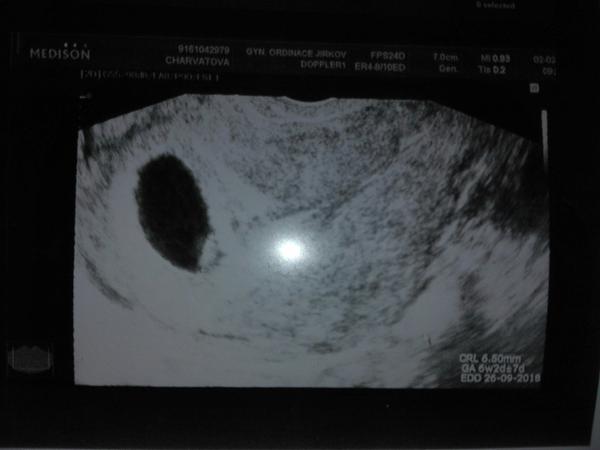

@natysnovec taky ste 6+2

@alexkisss jsem asi min...